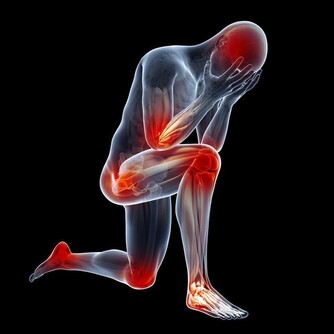

Mary最近開始,走久了就覺得關節有點沒力,應該要好好保養才是啊!

膝關節保養過猶不及,運動過度容易加速磨損,運動不足又容易使關節僵硬,但適度運動的確可以延長膝關節的使用時間!